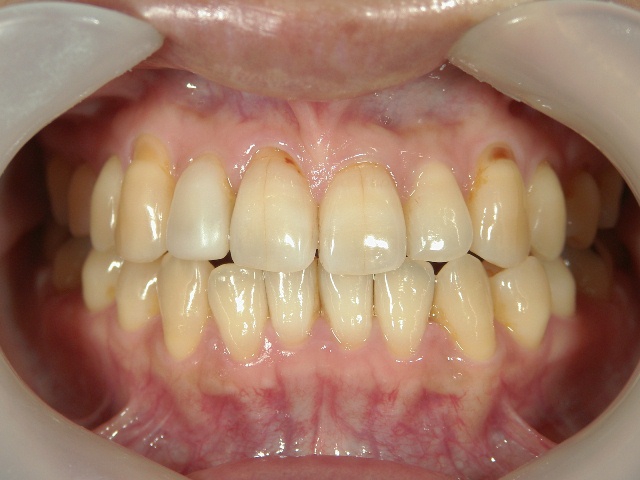

矯正歯科 治療前 正面

矯正歯科 治療後 正面